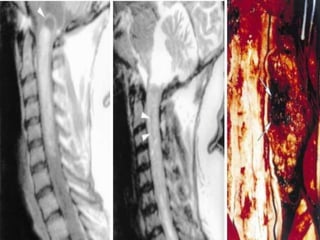

RM COLUNA

CERVICAL/TORÁCICA/LOMBAR

 Hérnia de disco

 Canal medular